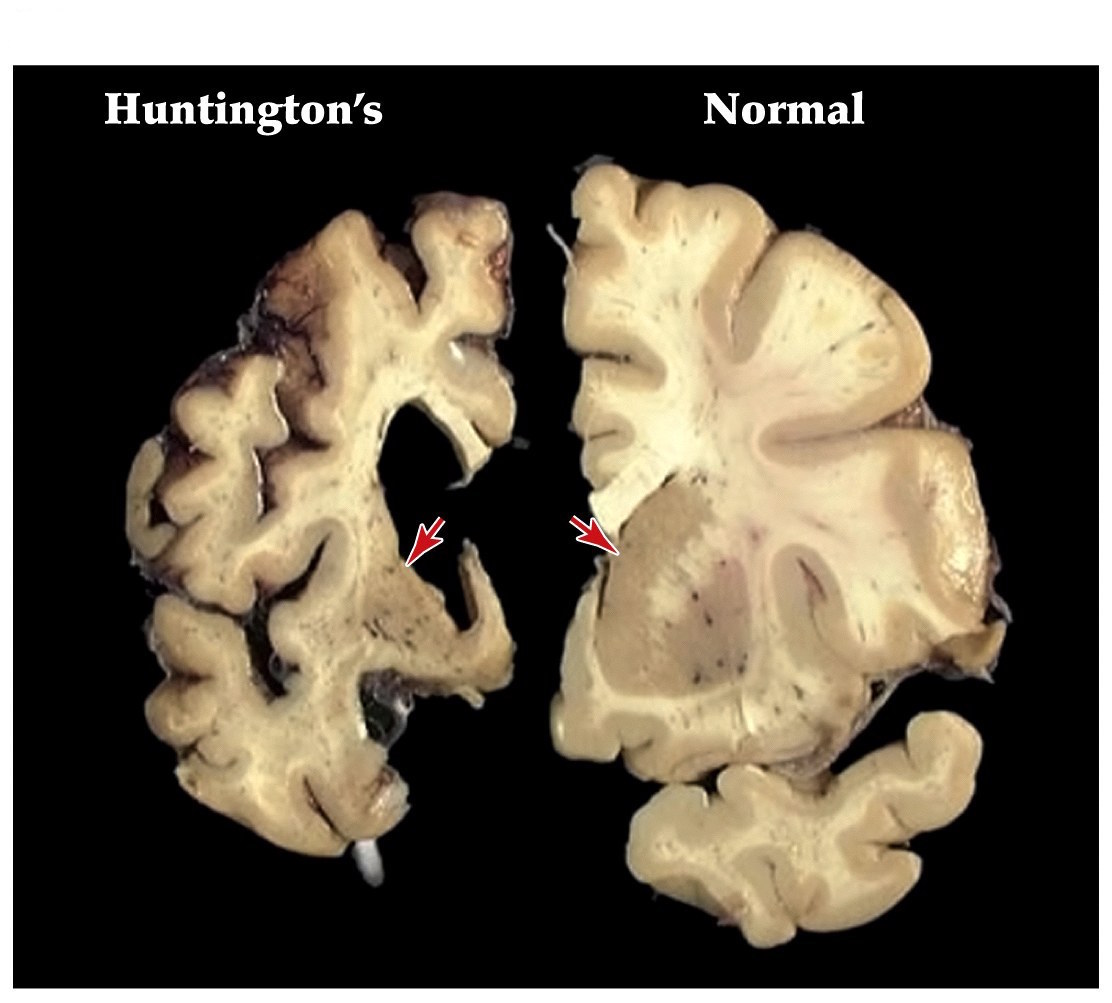

Huntington’s disease

- One of the most common inherited neurological diseases

- Progressive deterioration of the caudate and putamen that project to the GP externa (indirect pathway)

- Leads to a movement disorder consisting of rapid jerky motions with no clear purpose

- Dominantly inherited– strikes around midlife

- Patients develop depression, mood swings, and abnormal movements (striatum)

- Caused by alterations in a single gene that encodes the huntingtin protein

- Huntingtin protein has an expansion of a CAG trinucleotide repeat, resulting in an extended polyglutamine repeat. Leads to aggregation of proteins and cell death

Hypokinetic and hyperkinetic disorders summary

- Parkinson's– hypokinetic disorder. More tonic inhibition of thalamus and decreased excitation of frontal cortex

- Huntington's– hyperkinetic disorder. Less tonic inhibition of thalamus and more excitation of frontal cortex